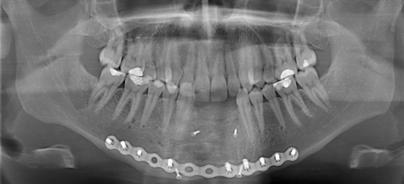

Rehabilitation in der Unterkieferfront

Die präimplantologische Knochenaugmentation ist heute ein wichtiges und herausforderndes Thema in der zahnärztlichen Implantologie. Bei jedem implantologischen Kongress wird dieses Kapitel aufs Neue diskutiert. Die vertikale Augmentation stellt alle implantologisch tätigen Chirurgen vor eine besondere Herausforderung. Dabei gibt es diverse dokumentierte und publizierte Methoden zu diesem Thema. weiterlesen